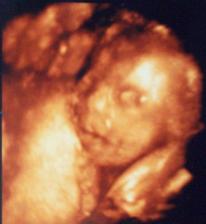

22.6. 09- 9.UZ- 18+1tt, váha 64kg. Vše v pořádku a zřejmě budeme dvě holčičky 🙂. U jedné si paní dr. nebyla 100% jistá, ale říkala, že si myslí, že je to taky holčička. Váží 192g a 200g. Klidový režim zůstává i nadále, ale už nemusíme ležet, občas můžu i na procházku, takže supééééér 🙂. 29.6. nás čeká 3D UZ a 8.7. velký genetický UZ ve 20+3tt.

8.7. 09- 10.UZ- 20+3tt, velký UZ dopadl na výbornou 😉. Všechno je naprosto v pořádku a máme na 90% potvrzené dvě holčičky 🙂. Takže to bude Eliška Gabriela a Magdaléna Marie.